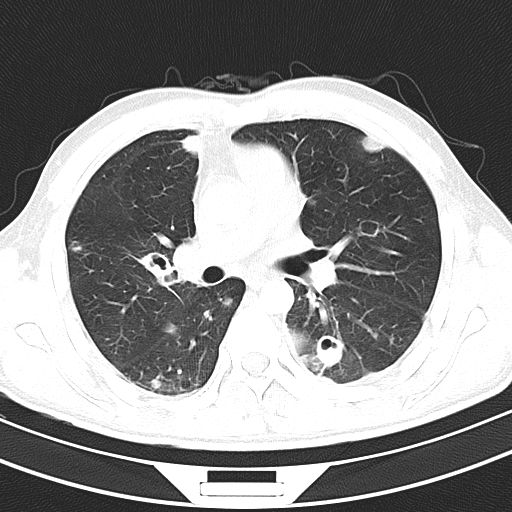

叶间裂下坠,从CT上看,就感染的肺组织膨胀了!

肺炎克雷伯杆菌,就是这么骄傲的细菌,非常喜欢自我膨胀!控制不住的自我膨胀!

最后,再来回望一下,什么是叶间裂下坠。

肺炎克雷伯杆菌,你就膨胀吧!